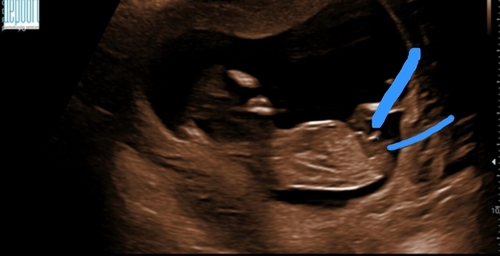

Het bovenste streepje is denk ik de navelstreng en dat onderste streepje daar pas je de nubtheorie op toe. Dat onderste streepje wijkt wel iets af naar boven dus in deze zou je kunnen zeggen hey word een jongen. Bij een meisje schijnt hey echt horizontaal te liggen maargoed het is maar een theorie

Onder de navelstreng zie je inderdaad dat de nub naar boven wijst. Plaats je foto ook eens in het algemene nub theorie topic :) weet zeker dat je alleen 馃挋馃挋馃挋 krijgt 馃グ